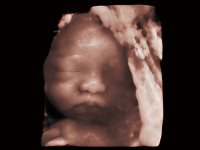

夢(mèng)溪?P80以“關(guān)愛女性”為基石,提供全方位的解決方案,量身定制以滿足女性的健康需求,涵蓋婦科、生殖健康檢查、產(chǎn)前篩查及產(chǎn)后康復(fù)等領(lǐng)域。